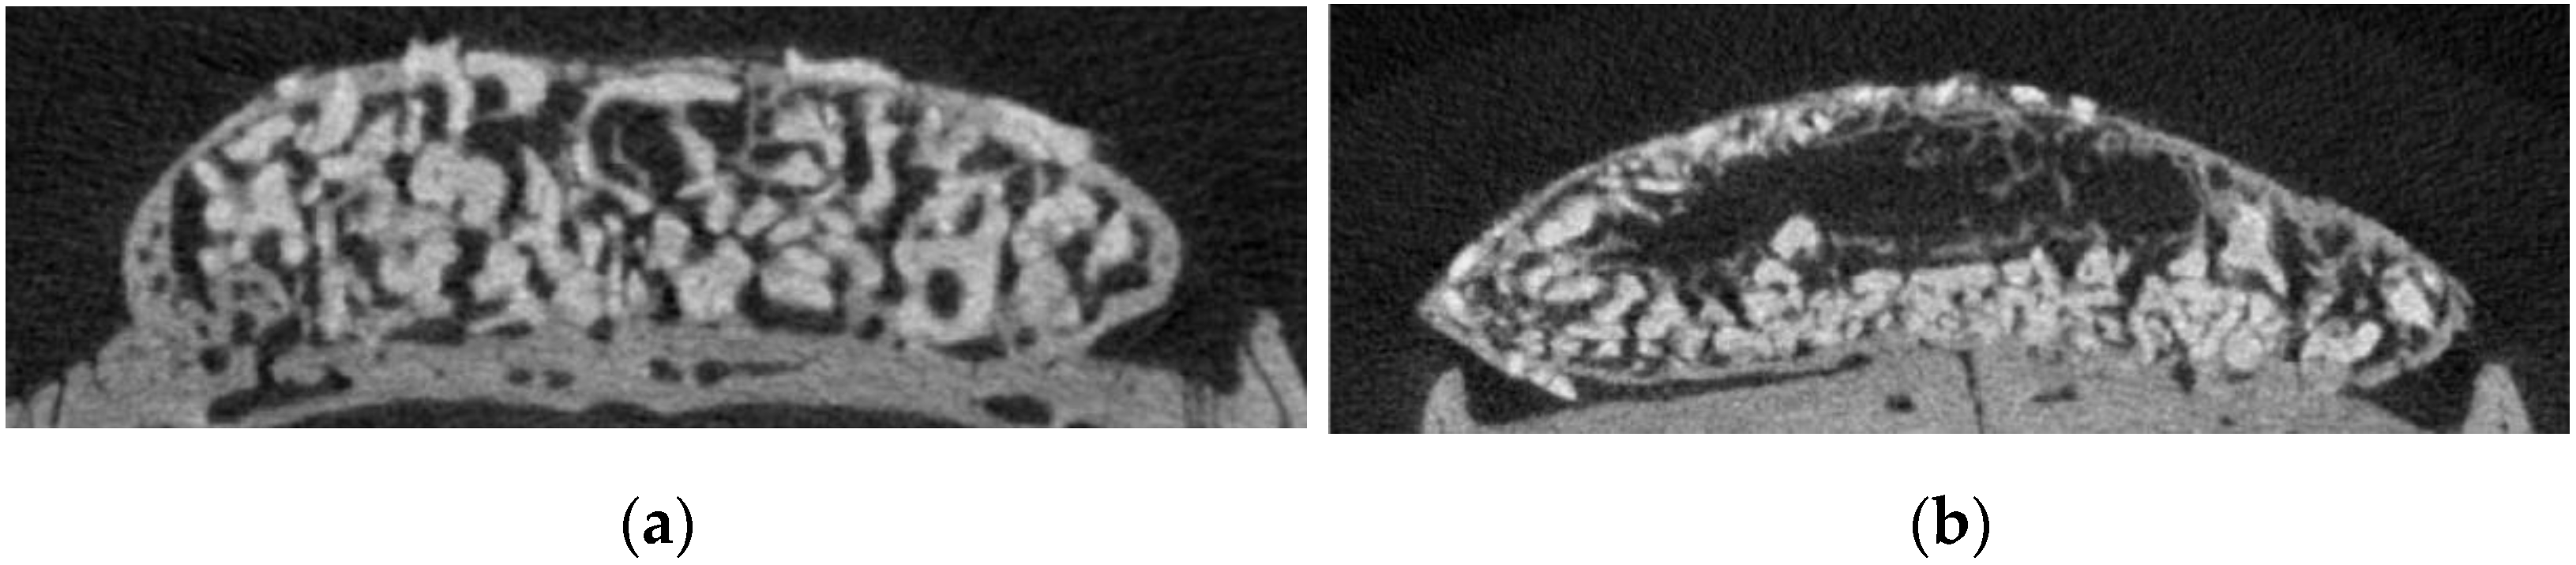

3.3. Histological Examination of the Changes in the Newly Formed Bone and Adipose Tissue